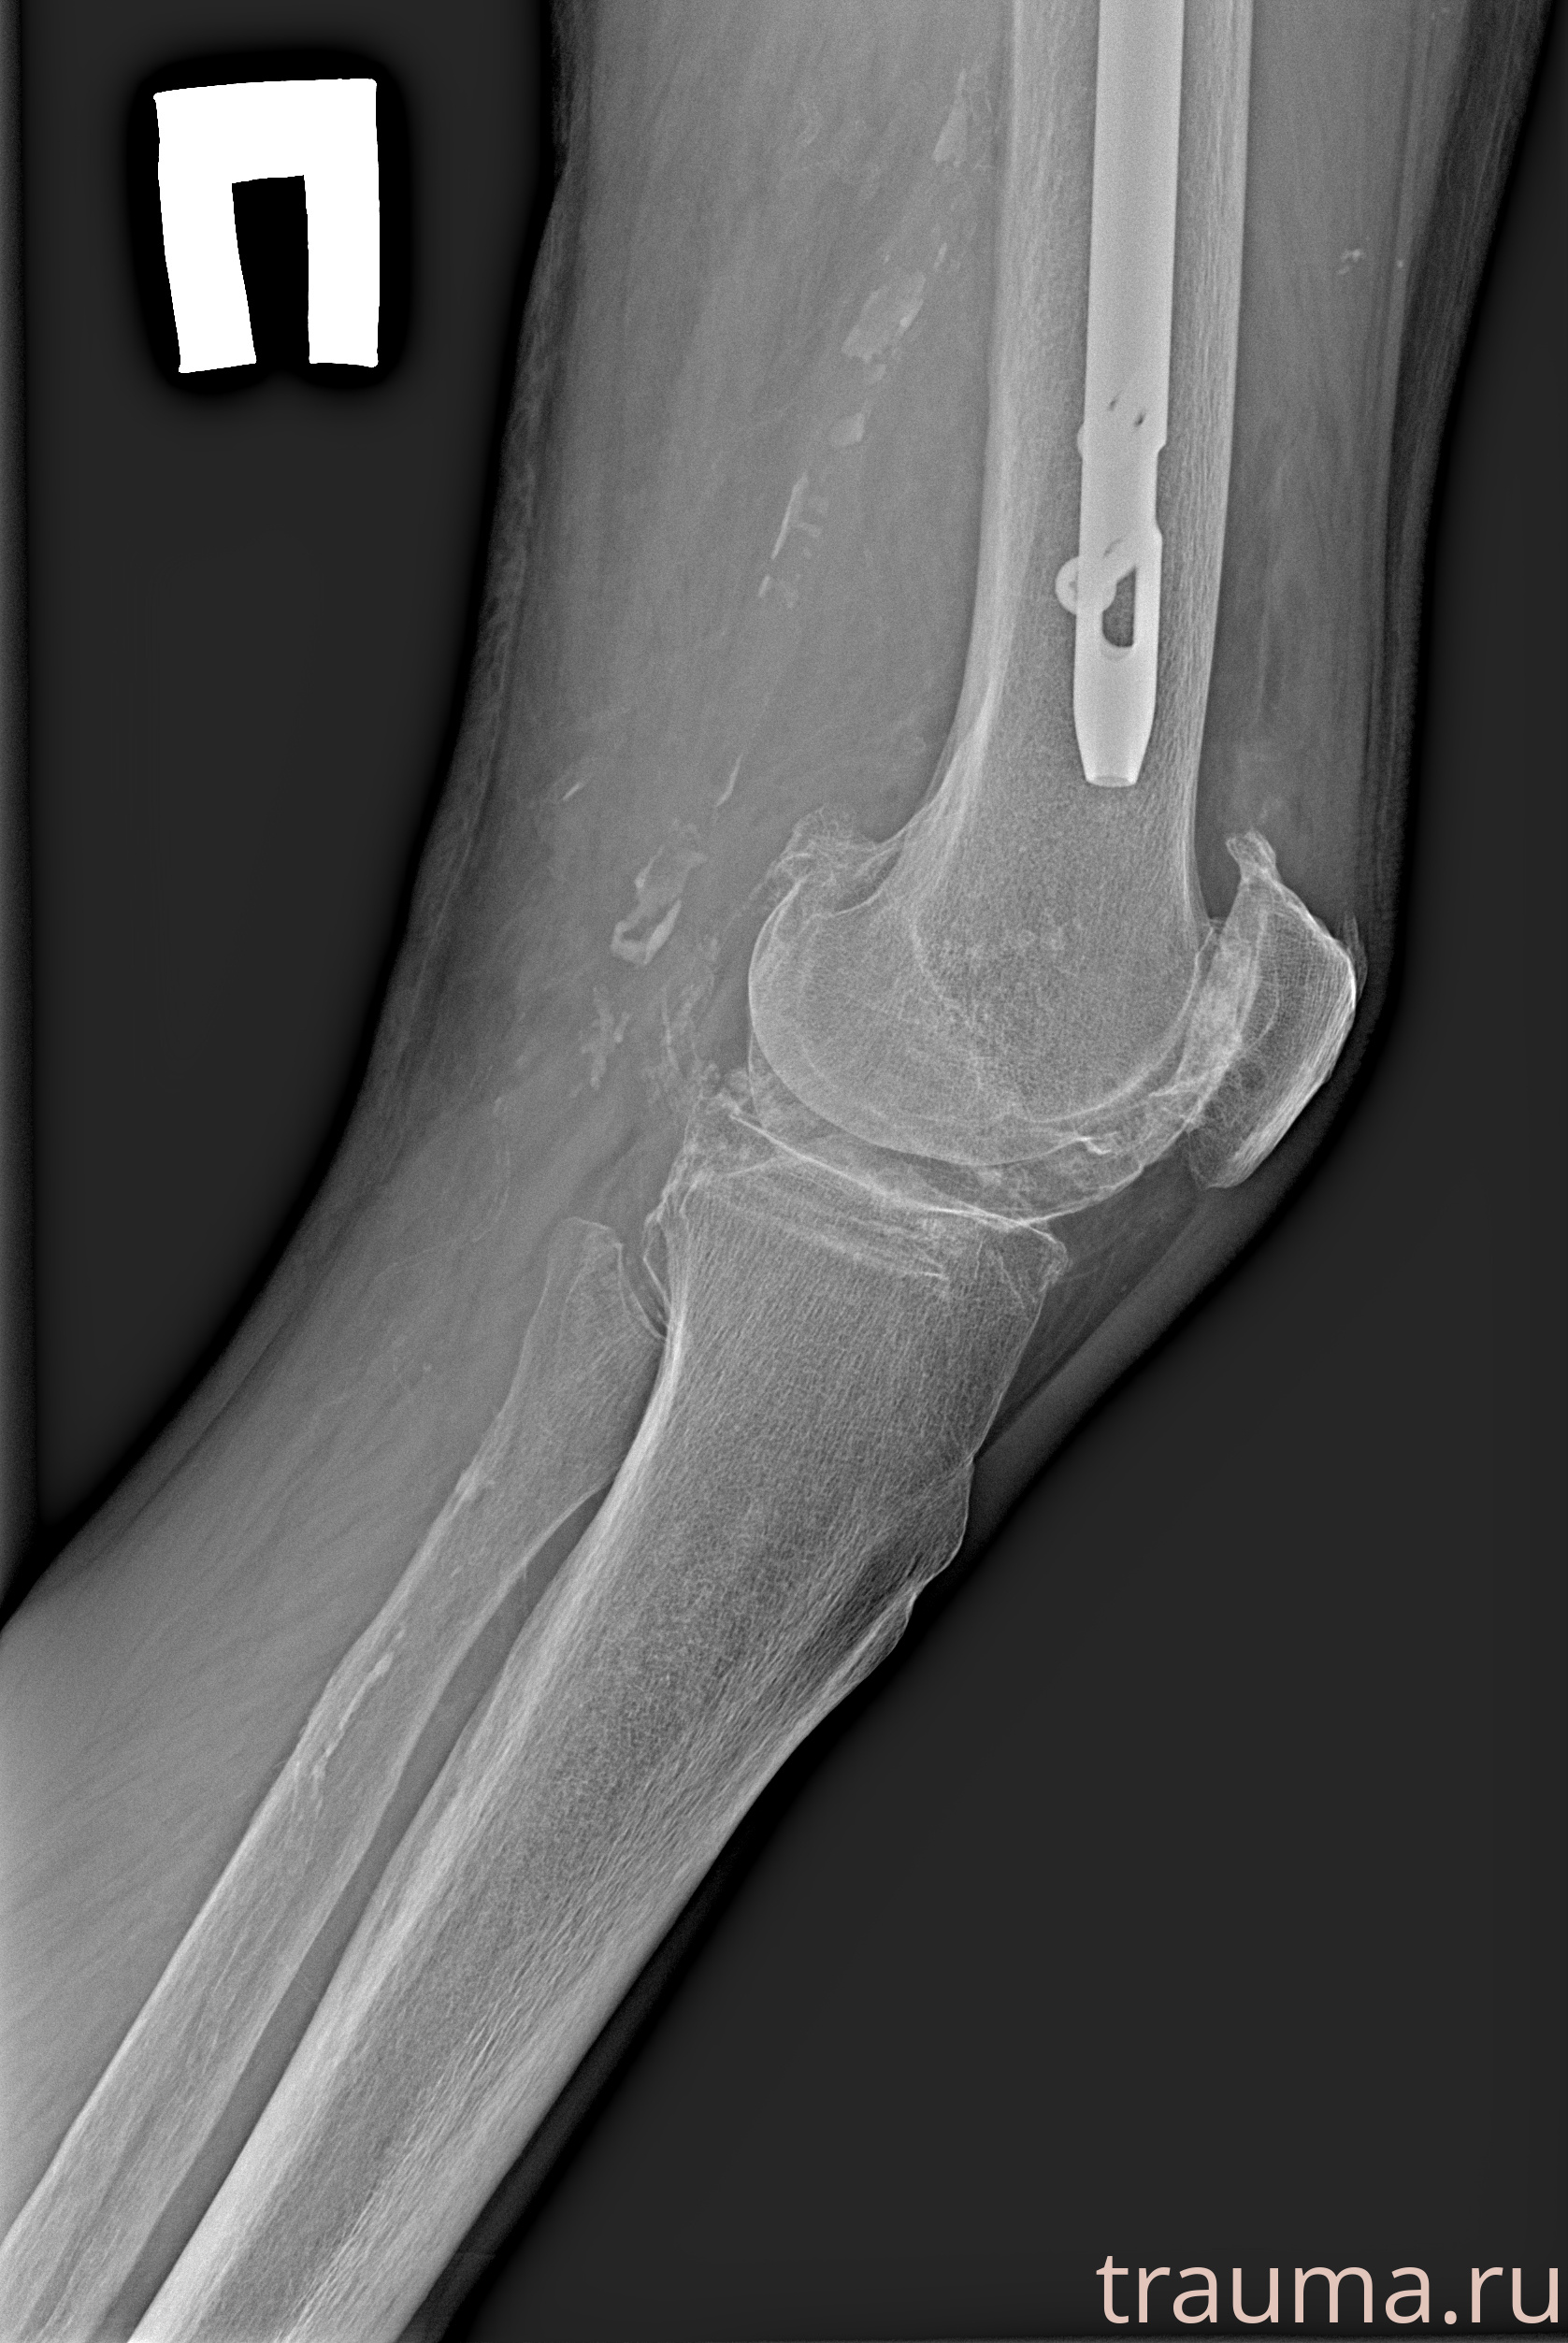

Рентгенограммы

Рентген на дому: по вашему адресу приезжает врач-рентгенолог, травматолог-ортопед с мобильным рентгеновским аппаратом, проводит диагностику травмы или заболевания, делает необходимые рентгенограммы, дает рекомендации по дальнейшему лечению. Получить качественные снимки в домашних условиях возможно благодаря уникальной методике, разработанной МосРентген Центром для института  Склифосовского